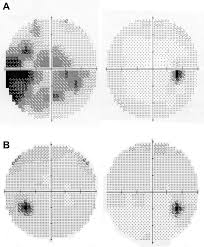

An enlarged blind spot is typically seen. Clinical features and differential diagnosis of acute idiopathic blind spot enlargement syndrome article abstract authors. A 35 year old patient underwent static visual field humphrey 30 2 and multifocal electroretinogram testing at 2 weeks and 4 months after the onset of acute idiopathic blind spot enlargement.

Hypocyanescent spots typically outnumbering the clinical lesions are seen. Prolonged retinal dysfunction revealed by multifocal electroretinogram technique. Kondo n kondo m miyake y.